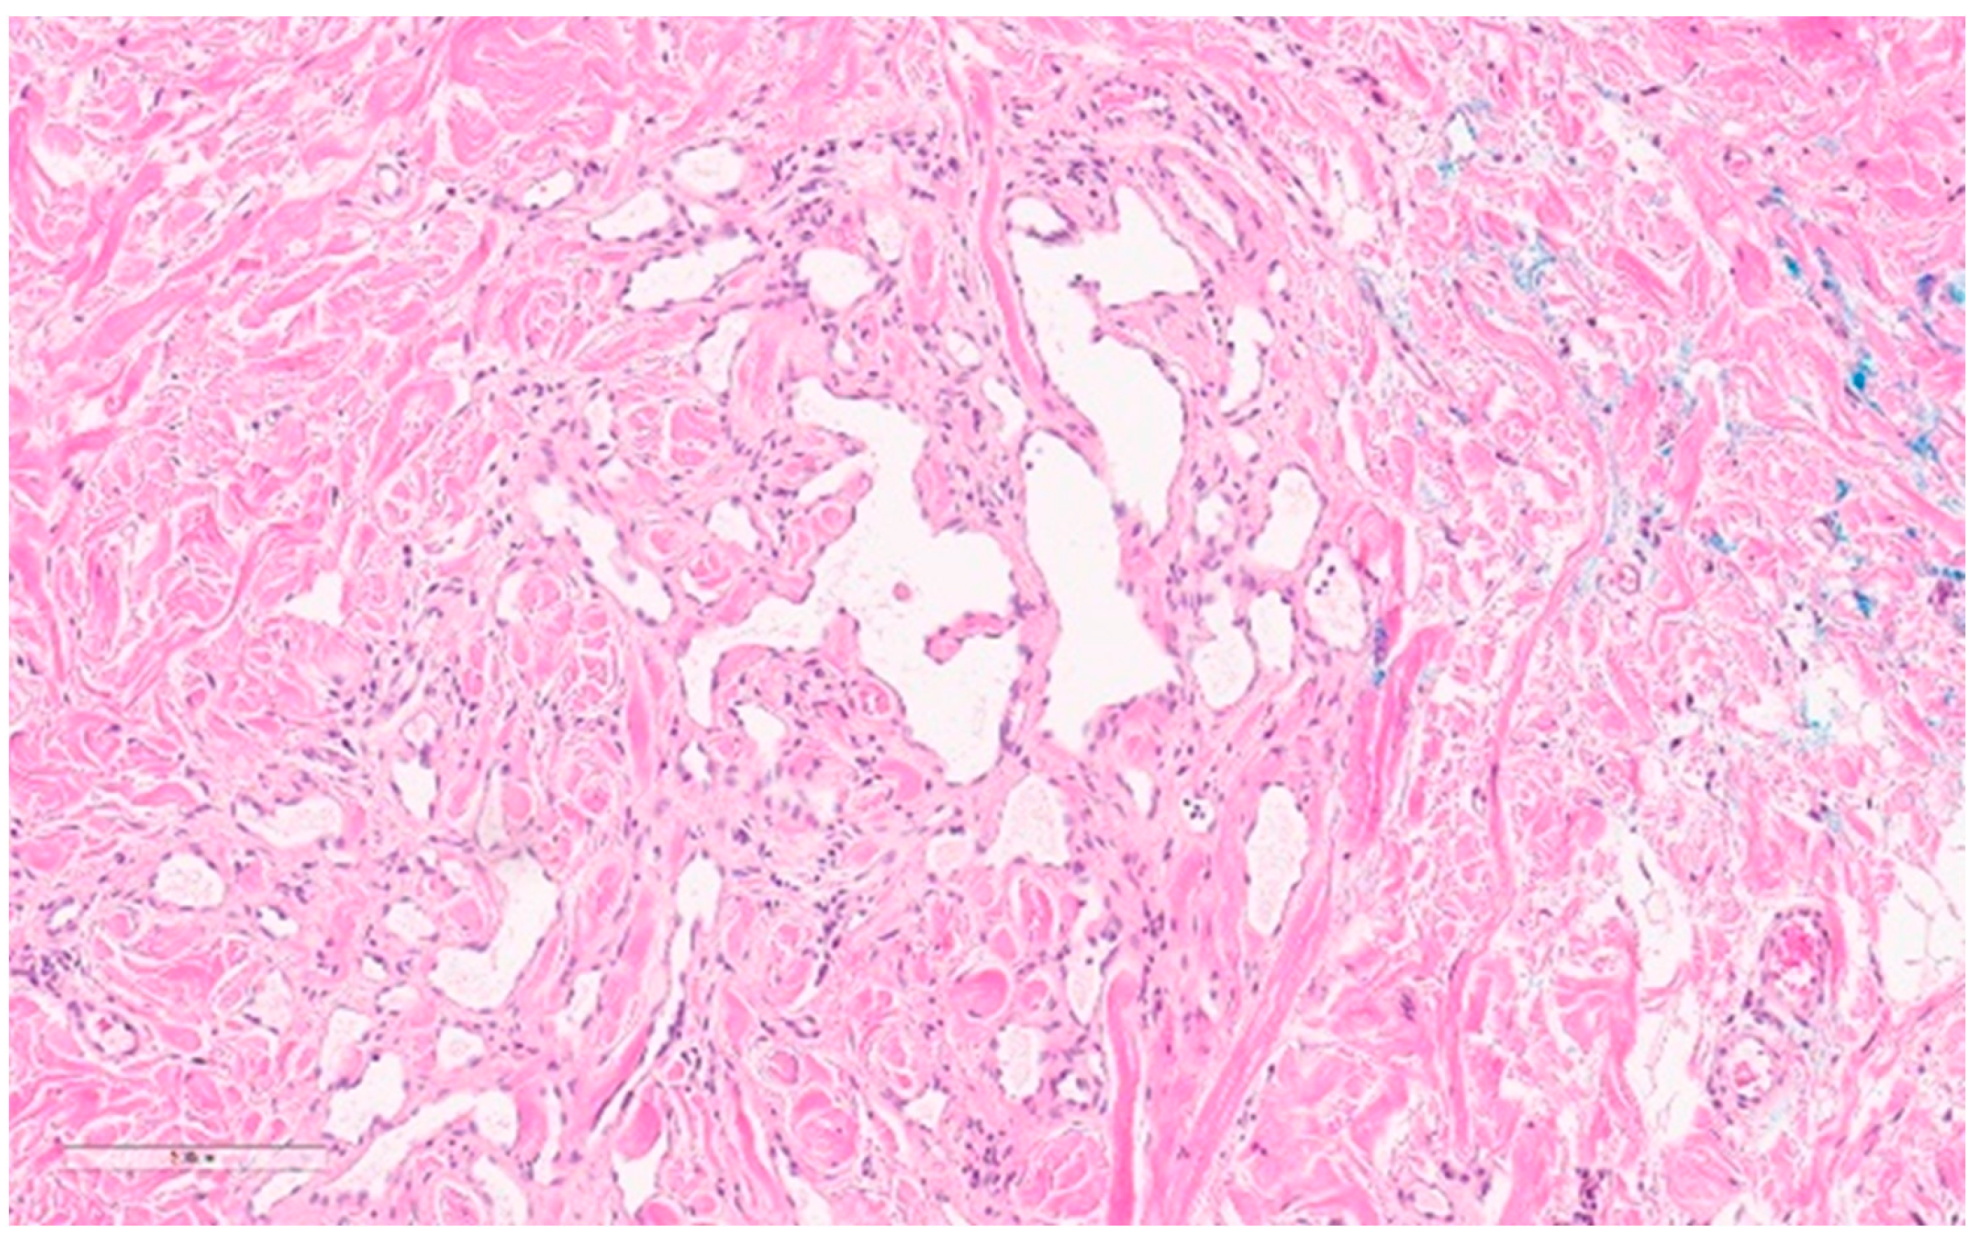

6.2. Atypical Vascular Lesion

Summary of Updates

| Hemangioma | 50 years old Female predilection Seen in 11% of autopsies Superficial palpable masses with skin discoloration Often incidental on screening mammography | US: variable definitions, difficult to differentiate from complex cysts or fibroadenomas MG: non-specific, well-circumscribed, can have calcifications related to phleboliths MRI: circumscribed masses with fibrous septa, fast enhancement and washout | Expect bleeding with biopsy FNA inconclusive and hypocellular CNB usually needed Dilated vascular spaces with thin-walled venous vessels | Rarely useful—very similar to angiosarcoma | Excision indicated- to rule out angiosarcoma and for risk of malignant transformation Note: much of this comes from older literature. More studies are needed. If not excising, should have radio-pathologic concordance and should be on surveillance. | Low malignant transformation No metastases |

| Atypical Vascular Lesion | 50 years old Must have history of radiation Single of multiple purple or brown papules Usually <5 mm | Usually uninformative | CNB or punch biopsy suggested Anastomosing lymphatic or capillary vessels in the dermis Flat to hobnailed endothelial cells Hyperchromatic nuclei | c-myc has 100% specificity but 80–90% sensitivity | Excise to negative margins | 10–20% recurrence rates Malignant transformation is rare, but th field defect from radiation exposure confers a higher risk of angiosarcoma |